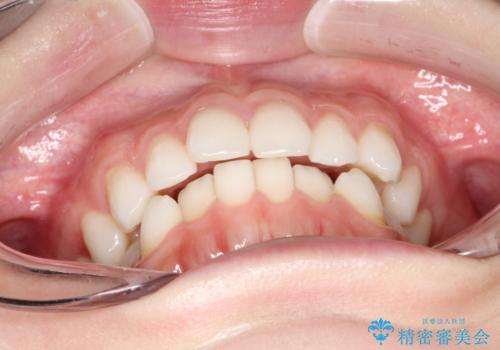

前歯のがたつきをインビザラインで目立たず矯正治療

- 上下の前歯のがたつきを主訴に来院されました。

目立たない装置がご希望で、インザラインによるマウスピース矯正にて治療を行うこととなりました。

使用時間を守っていただけたので、スムーズに治療を終わることができました。